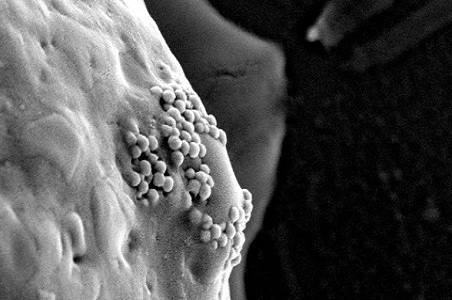

Các nhà khoa học Mỹ nhận thấy hạt nano vàng có thể phát hiện và tiêu diệt tế bào ung thư sót lại sau phẫu thuật cắt bỏ khối u, đưa tỷ lệ chữa khỏi bệnh ung thư lên 100%. Các hạt nano vàng bám trên bề mặt tế bào ung thư. Ảnh: D. S. Wagner. Khi bác sĩ thực…